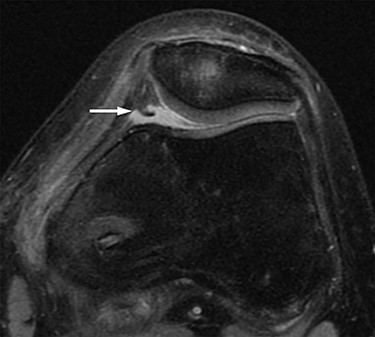

Two months postoperatively, the patient presented with the pain in the medial margin of the patella during walking and knee extension, and the pain continued when she was allowed to start rhythmic gymnastics at 6 months postoperatively. There was no evidence of swelling, crepitus and ROM restriction, and her apprehension sign was also negative. Pain was relieved by an intra-articular xylocaine injection. Postoperative MRI showed no clear injury to the cartilage of the medial PF joint, and the medial PF joint space and the size of the medial plica were almost the same as before surgery (Fig. 2). Based on these findings, left medial plica syndrome was suspected. Although the patient underwent conservative treatment consisting of analgesics and physiotherapy, there were no signs of improvement, and consent was obtained for undergoing arthroscopic surgery at 8 months after the initial surgery. Intraoperative arthroscopic findings with probing confirmed an unenlarged but hardened and thickened medial plica (Fig. 3). No injury to the patellar and femoral cartilage was observed. The synovial plica was considered the main cause of pain, and we performed a partial resection of the medial synovial plica. The pain and the tenderness at the medial margin of the patellar during walking and exercising had gradually improved after surgery. The Lysholm scale improved from 85 to 100 points. At 2 years postoperatively, the patient has currently no pain in the medial side of the patella, negative apprehension sign. She has returned to play in rhythmic gymnastics.

MRI. Axial proton density-weighted (TR = 3000, TE = 12) image before medial patellofemoral ligament (MPFL) reconstruction revealing medial synovial plica (white arrow). The medial patellofemoral joint space and the size of the medial plica after MPFL reconstruction are almost the same as before surgery. There are no clear signs of injury to the cartilage in the patellofemoral joint.